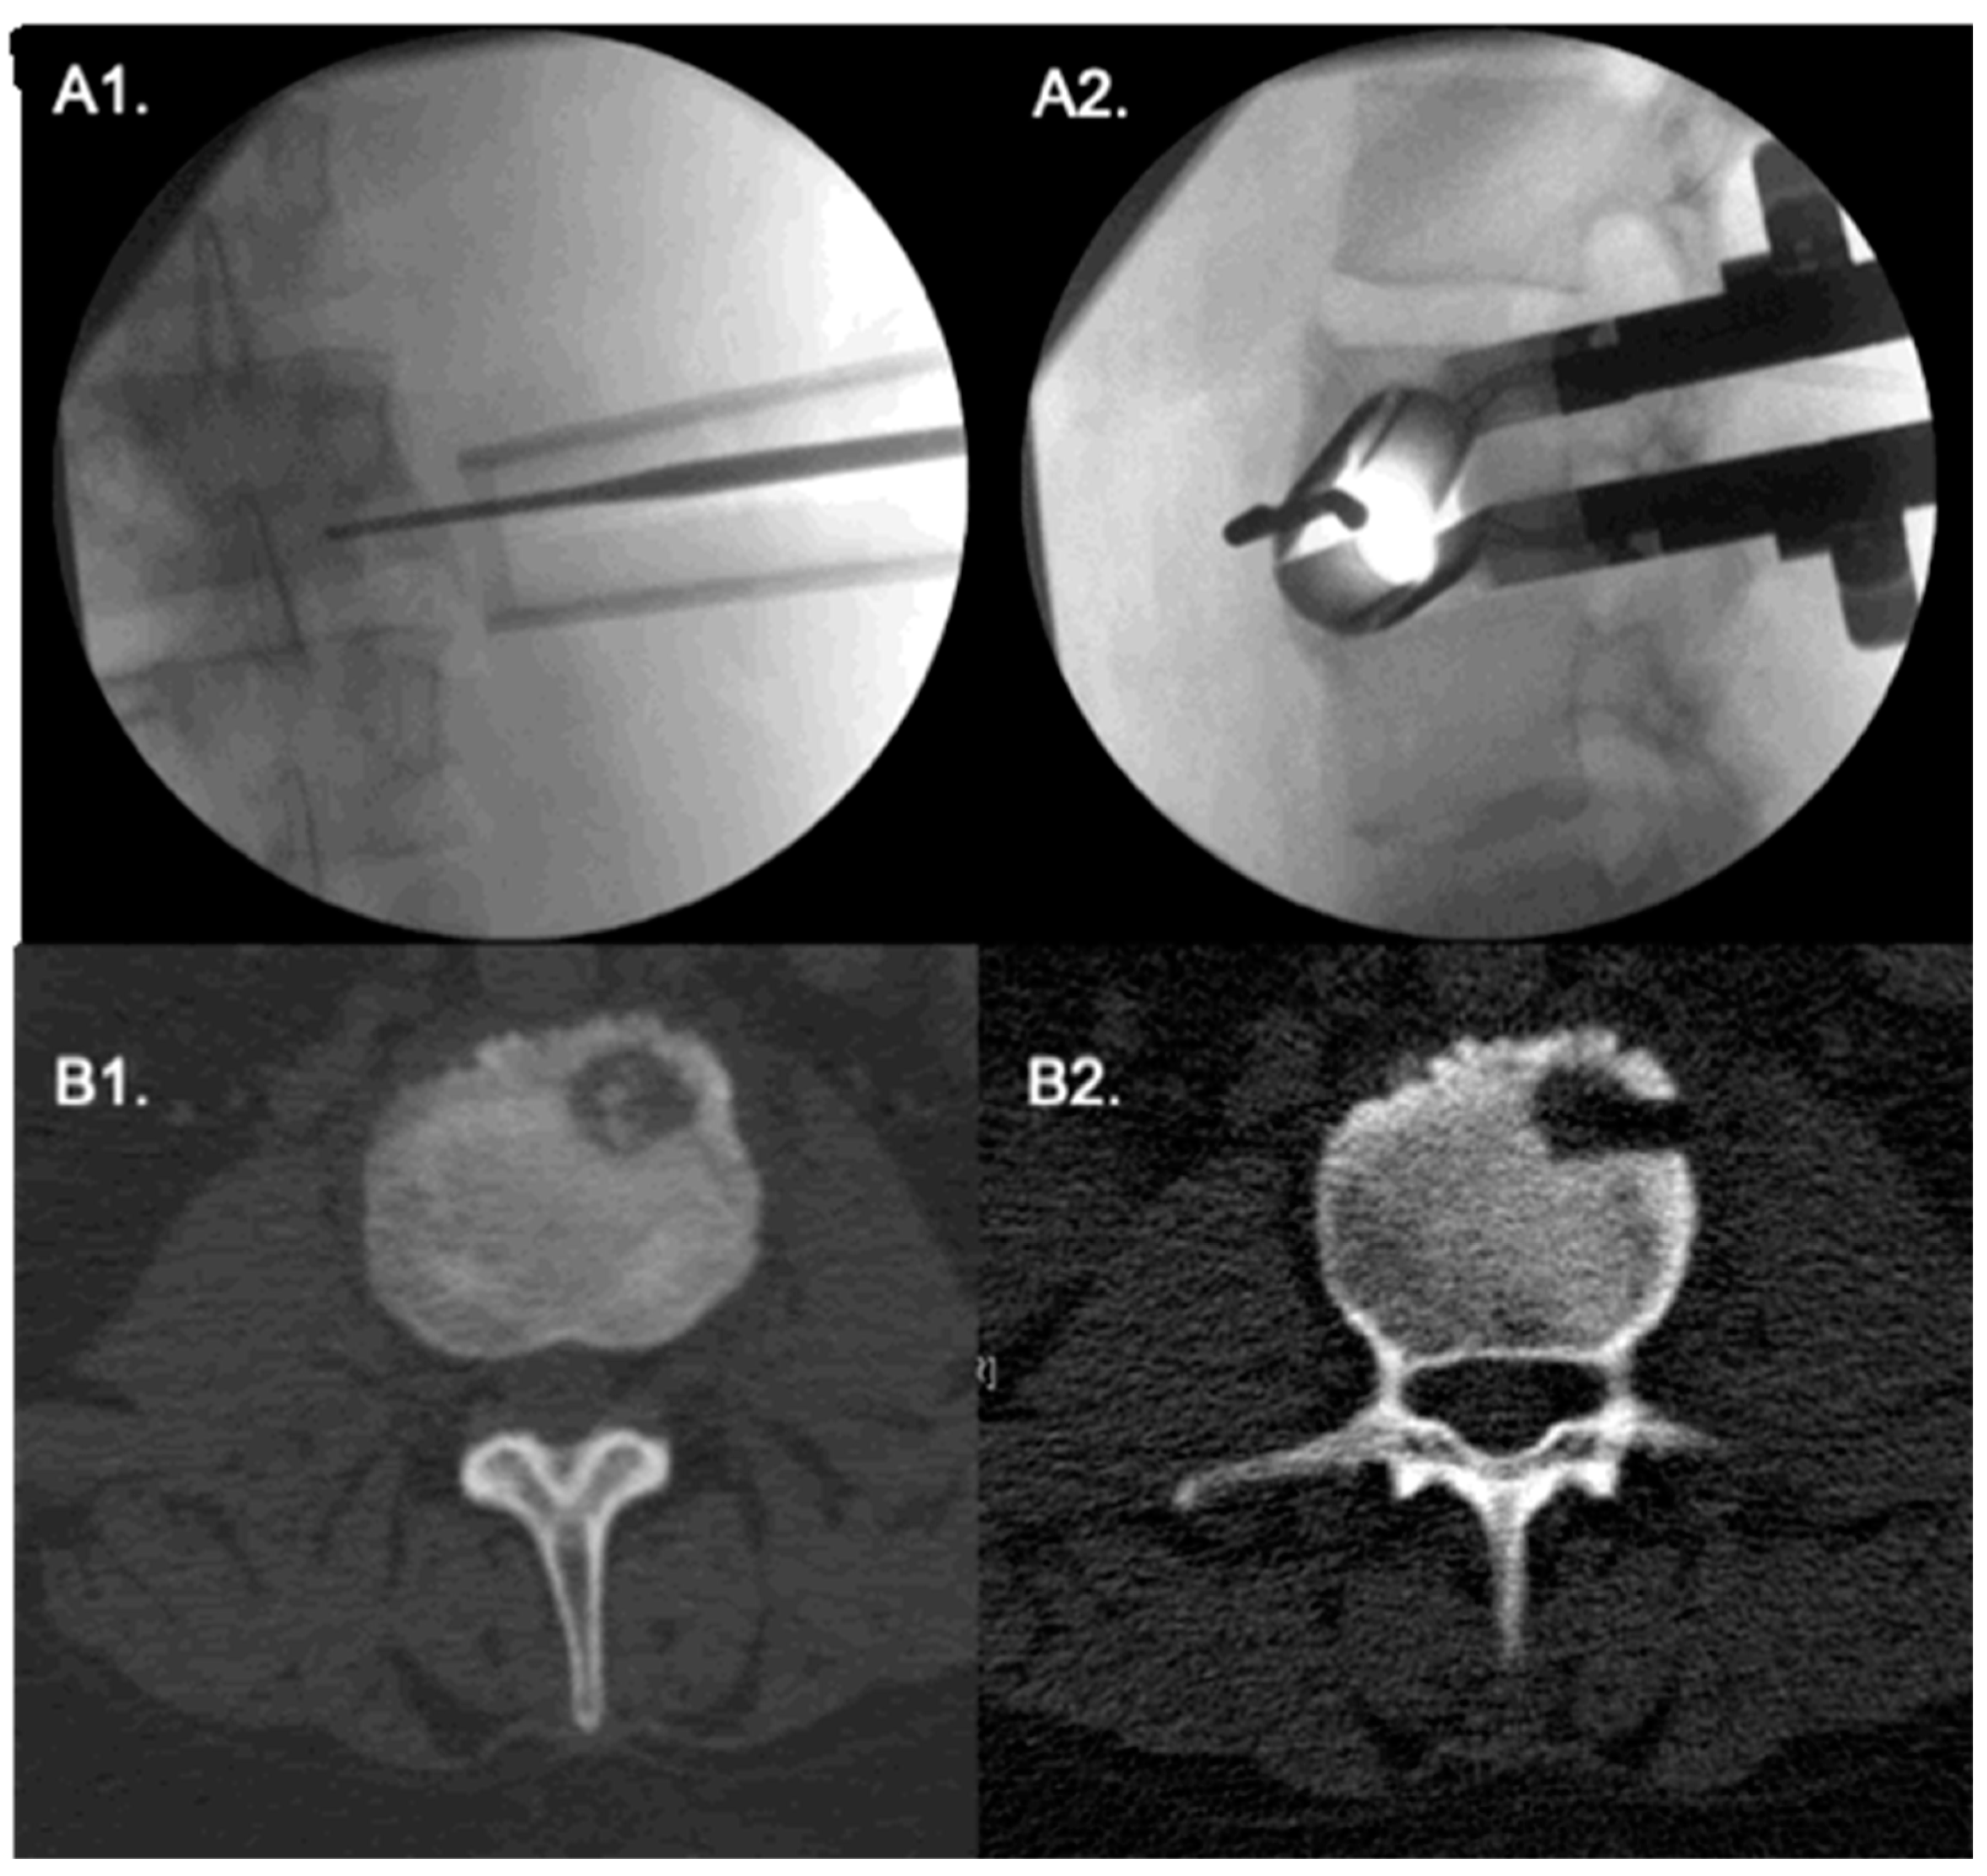

Surgical Technique